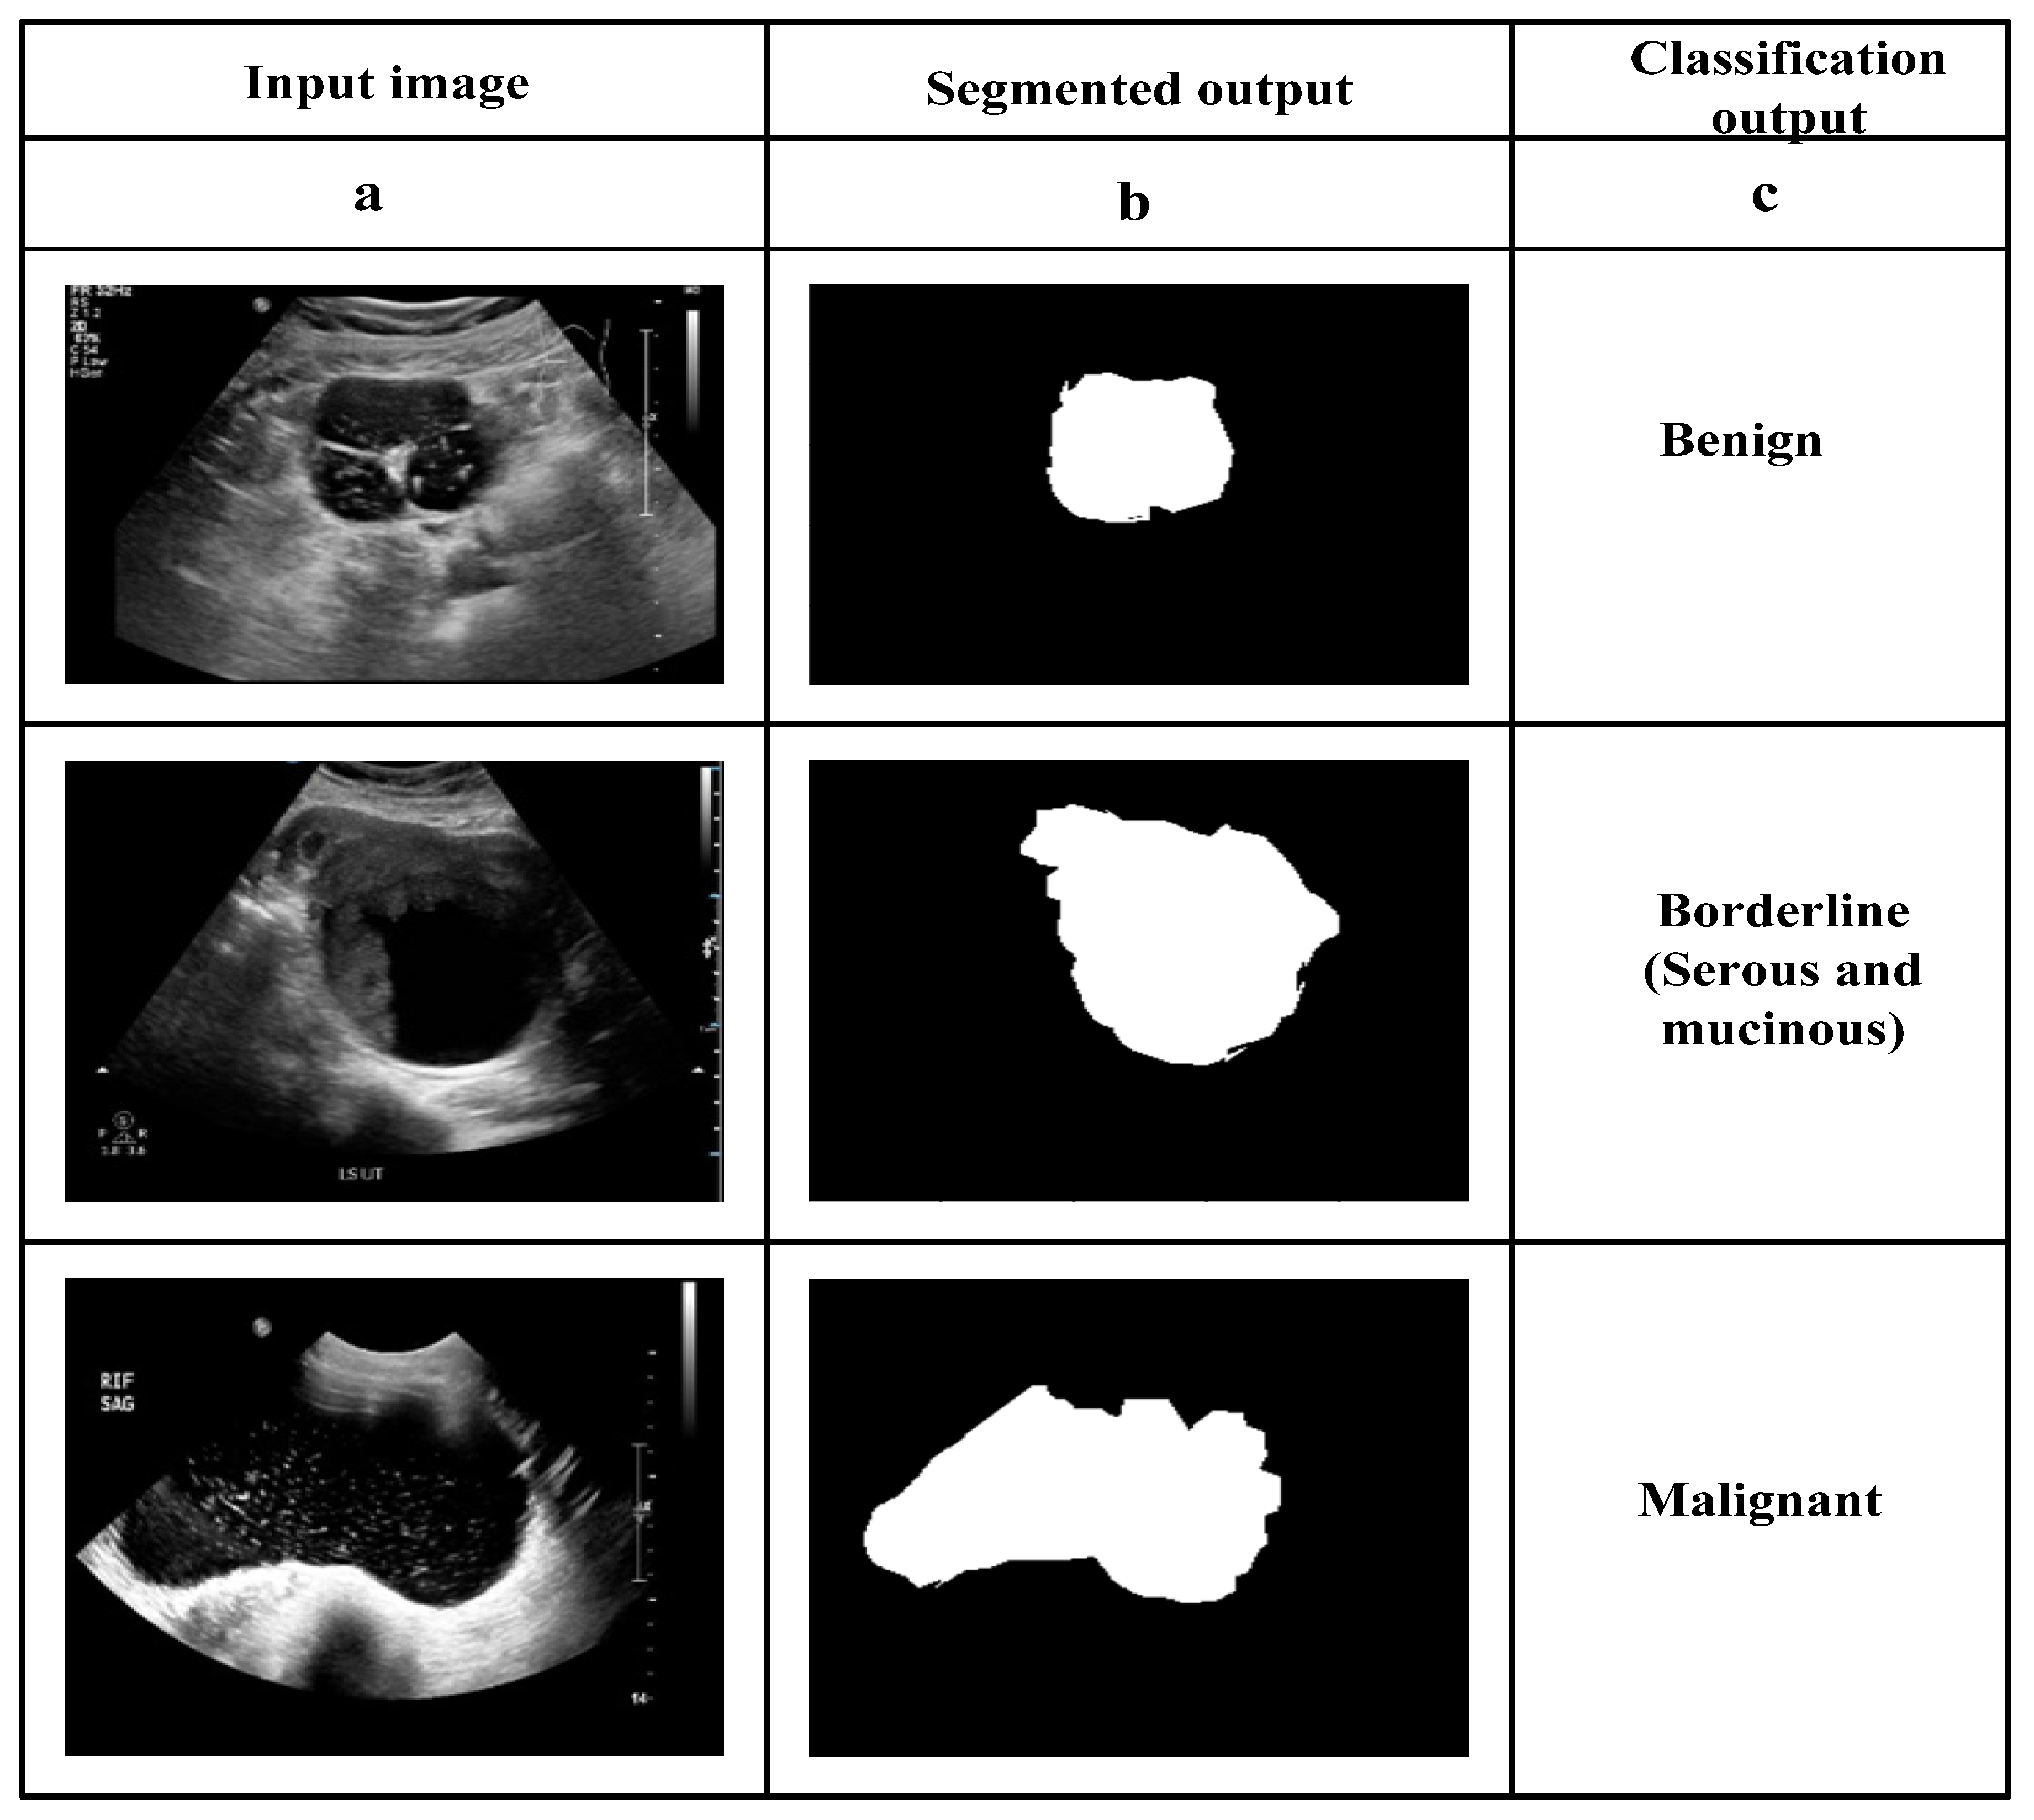

2.3. Segmentation Using 3D Tsallis Entropy-Based Multilevel Thresholding

2.5. Classification Utilizing EGNNN